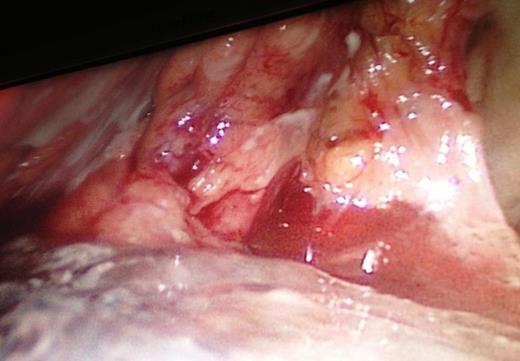

The intraoperative extension of the pancreatic necrosis that involves the entire gland.

Our patient's clinical deterioration precluded the use of preoperative ERCP/MRCP. Clinical suspicion for hollow viscus injury prompted diagnostic laparoscopy. Necrotic and hemorrhagic pancreas precluded any intraoperative attempt to accurately characterize extent of ductal injury. Looking retrospectively, we acknowledge that, if we were able to diagnose ductal transection pre/intraoperatively, our management would have drastically deferred towards distal pancreatectomy.